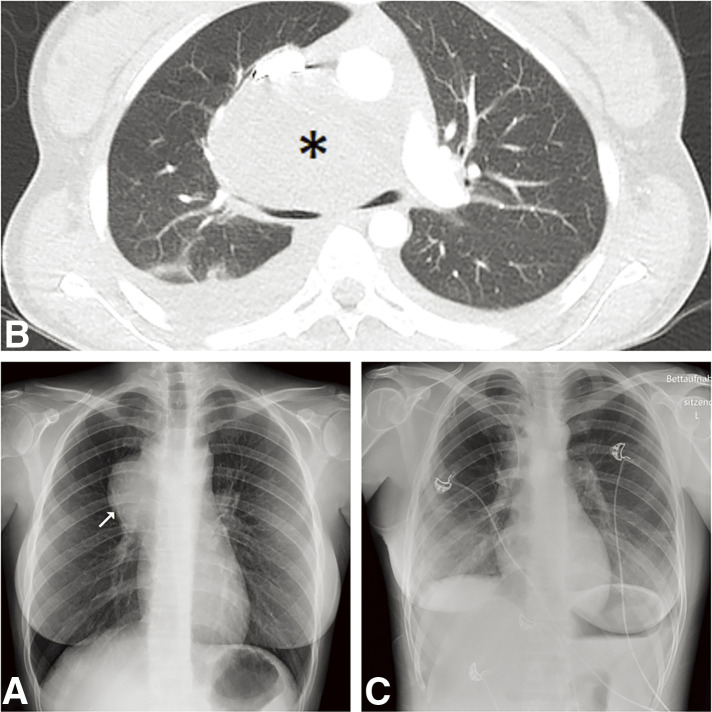

Bronchogenic cysts (BCs) are often incidental findings during imaging and can cause compressive symptoms depending on their location and size. Infections of mediastinal BCs are serious complications that can lead to life-threatening mediastinitis. The impact of severe acute respiratory syndrome coronavirus 2 on BCs remains largely undocumented. We present a unique case of a purulent-inflammatory mediastinal BC complicated by sepsis in the context of a Coronavirus Disease 2019 infection. The Coronavirus Disease 2019 infection may result in a bacterial superinfection of the BC. However, the transmission path requires further investigation. For the surgical excision, we opted for a two-step surgical approach: thoracoscopic incision and drainage in the acute setting, followed by elective thoracotomy and resection of the BC. We confirm the safety and favorable outcome of this approach.